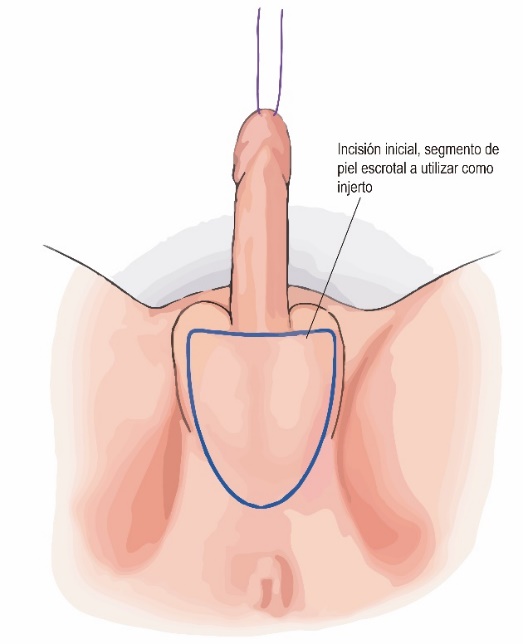

Para tapizar la neo vagina se puede utilizar solo piel del pene en casos muy favorables, o adicionar otras estructuras. La técnica más frecuentemente utilizada agrega un injerto de piel libre escrotal (Figura 3) que luego es modelado sobre un dilatador y que se sutura al cilindro de piel peneana para mayor profundidad. También se puede usar un injerto de piel libre desde otra zona dadora (generalmente inguinal o hipogástrica) o flaps de peritoneo disecados de forma robótica.

En la técnica desarrollada por Dr. Guillermo Mac Millan, se utiliza un colgajo perineal de irrigación inferior además del escroto tratado como injerto libre (Figura 4). Otra alternativa para recubrir el canal vaginal, especialmente en cirugías de revisión y/o en personas trans que, producto de un bloqueo hormonal precoz presenten mínimo desarrollo de estructuras genitales masculinas, es el uso de algún segmento intestinal, principalmente colon sigmoides. Las ventajas de este último es el aspecto mucoso, la lubricación y la posibilidad de alcanzar mayor profundidad. Las desventajas son posible secreción de mal olor y el riesgo propio de una anastomosis intestinal.